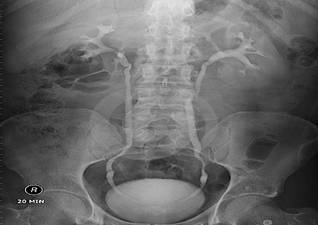

X线造影

Tips:其中B超简单、无创,可以用来初步筛查,但由于受到腹部肠气干扰,对于没有扩张积水的输尿管及结石显影模糊不清,并且受到检查设备及检查医师的经验水平限制。X线造影可以直观的将结石的剪影投射在一张平片上,就像平常我们照相般反应结石及肾脏集合系统的大致情况。B超、X线造影的缺陷在于,其影像都是二维平面,看到结石也仅仅是一个片面,CT三维成像则能提供一个三维立体的图像,将肾脏及其中的结石直观立体地呈现在我们面前。这三者对于医师评估病情,决定手术方式、手术入路具有非常重要的作用。这就是为什么我们需要给每个结石病人做多种检查的原因,因为它们各有优缺点,互相验证,互相弥补,通过完善的检查,可以让患者结石的位置和形态在主刀医生的大脑中清晰的呈现!